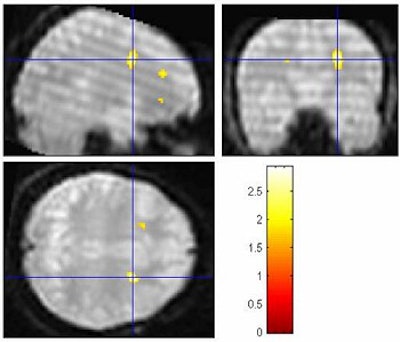

An event-related MR design was used for collecting the functional MR images. As expected, the polygraph picked up the liars, Faro said. But the fMRI scans showed significant differences in activation patterns when subjects were lying. Results showed the anterior cingulate, limbic lobe, and inferior frontal regions to be active during the deception process. However, when telling the truth, activation was predominantly seen in the temporal lobe and lentiform nuclei regions.

When the subjects were telling the truth, they didn’t have activation in those regions, he said.

"Truth-telling is a normal process. There’s no conflict or inhibition of response and emotional content," he said.